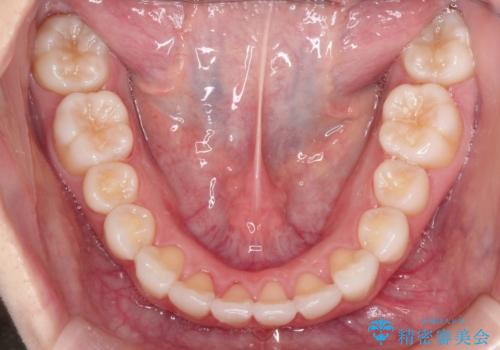

インビザラインで出っ歯を改善する 抜歯をしないinvisalign治療

- 非抜歯・遠心移動による前突の改善をマウスピースにて計画した。

非抜歯矯正の場合、大きく前歯を下げることはできませんが、奥歯の遠心移動や歯のサイズダウンにより歯軸を立て、見かけ上の出っ歯感をある程度改善することができます。